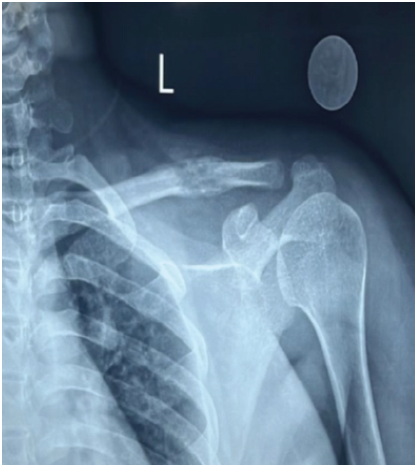

X-ray of the left shoulder revealed an osteolytic lesion in the middle third of the clavicle (Fig. 1).

Figure 1: Zero magnification X-ray of the left shoulder – anteroposterior view shows a 3 × 1 cm lytic lesion with surrounding areas of sclerosis.